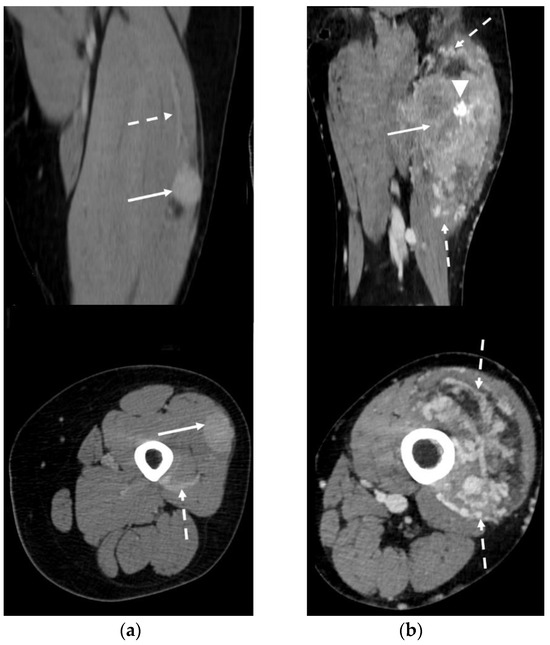

3.5. CT Features

- Slight low density and inhomogeneity on unenhanced CT